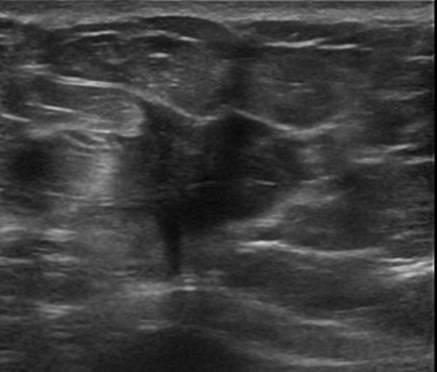

Ung thư vú

Ung thư vú - Ảnh 5

» Thông tin: Nữ giới – 72 tuổi.

» Lâm sàng: Khối tuyến vú.